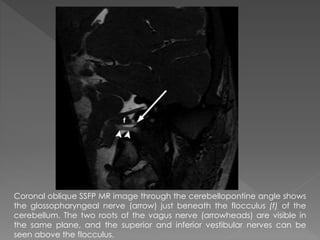

Coronal oblique SSFP MR image through the cerebellopontine angle shows

the glossopharyngeal nerve (arrow) just beneath the flocculus (f) of the

cerebellum. The two roots of the vagus nerve (arrowheads) are visible in

the same plane, and the superior and inferior vestibular nerves can be

seen above the flocculus.